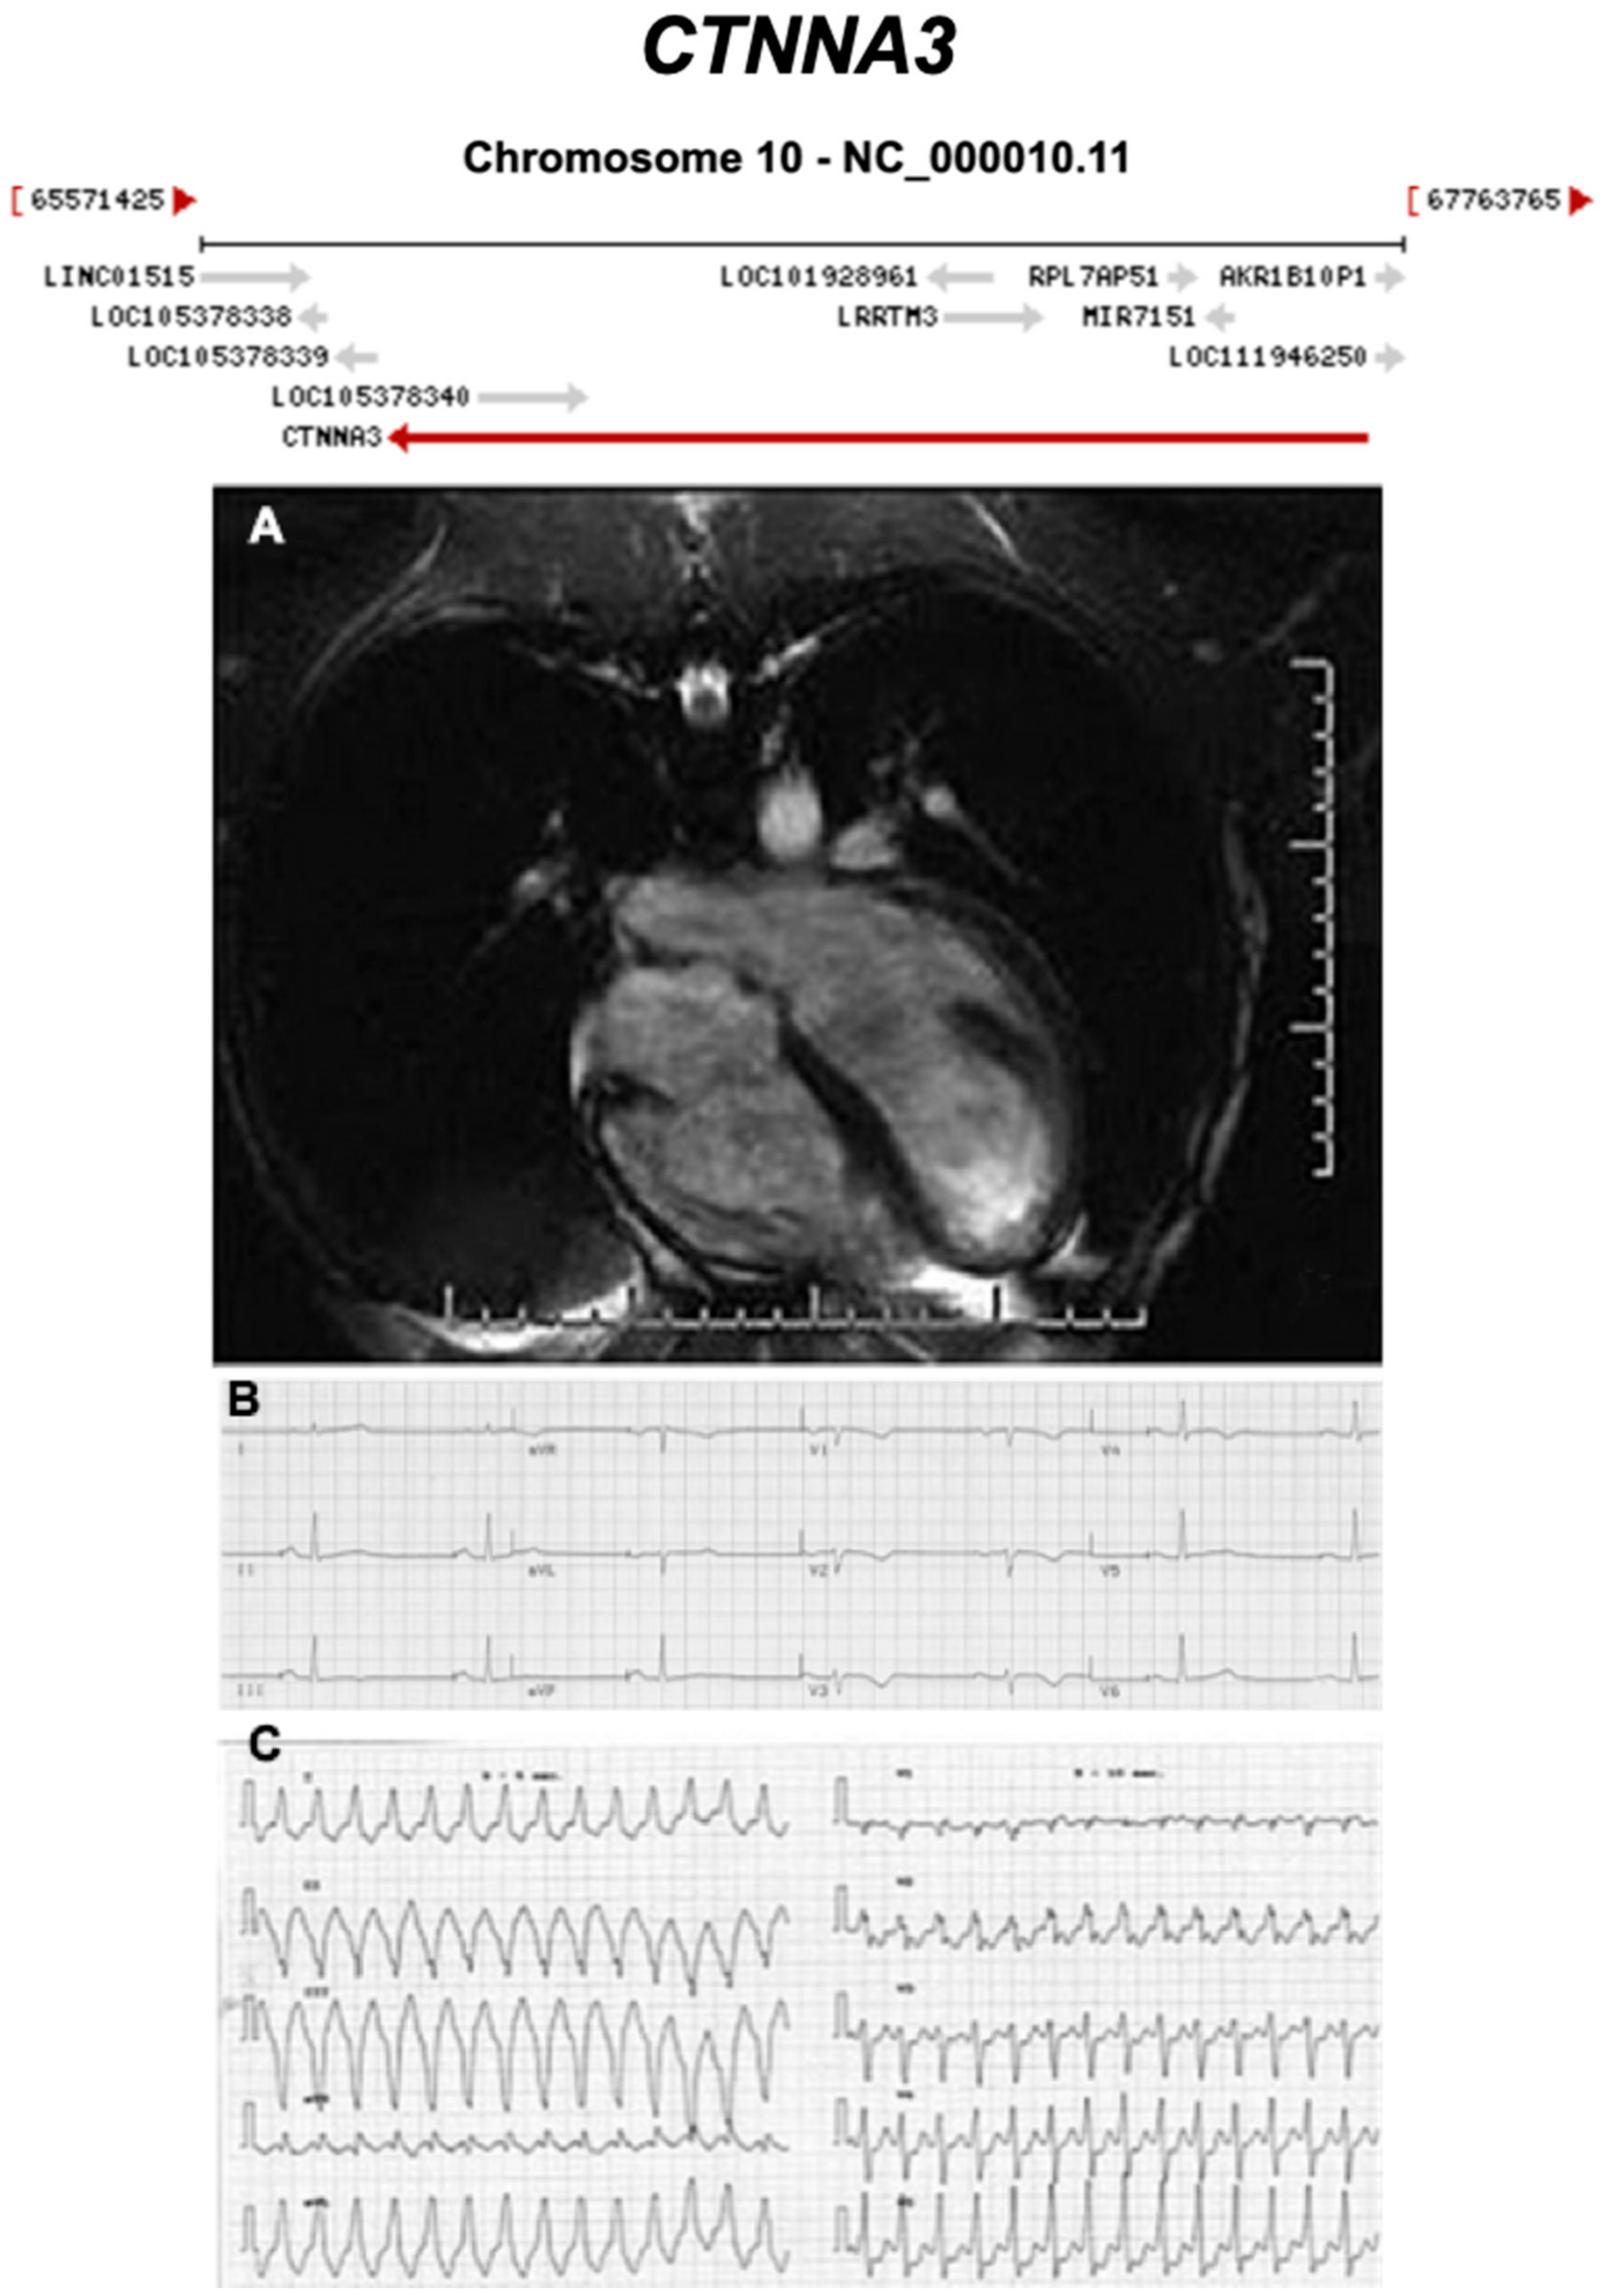

Figure 14.

Exemplar MRI and ECG finding found in ACM patients with CTNNA3 mutations. (A) CMR of a patient with CTNNA3 p.val94asp mutation showing marked right ventricular dilatation; (B) 12-lead ECG of the same patient showing a first degree heart block and T-wave inversion in V1–V4; (C) sustained ventricular tachycardia, with left bundle-branch block and left axis deviation. Reproduced with permission from van Hengel et al. (2013) [45].